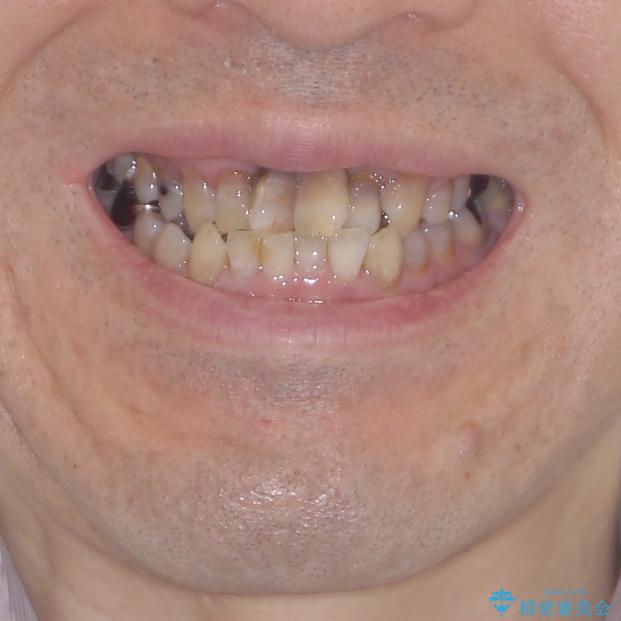

上顎の狭窄歯列 インビザラインによる拡大矯正

- 前歯の叢生と臼歯のクロスバイトを気にして来院された患者様です。

しかしながら、歯列を側方に拡大することができ、その後はインビザラインにて叢生を解消することができました。